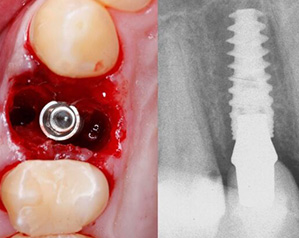

瑞典诺贝尔Active

瑞典Nobel是全球第一大种植体生成厂商,由现代种植牙之父Branemark教授合伙创立,其系统可分为骨水平和软组织水平,广泛适用于不同的骨质类型,几乎能解决所有的适应症,是深圳博爱曙光口腔数字化种植战略联盟中的重要合作伙伴,其中,Replace® CC更被广泛运用于针对所有适应症的美学解决方案中。

广泛适用各类缺牙症状,不管是松质骨、拔牙窝还是前牙美观区,都能依赖其独特植体设计实现即刻种植和即刻负重。

要求严苛时,Active逐级扩张的锥形主体、双钻刃的尖端可实现较小骨切割,保持高稳定性;反锥形冠状和内置平台转移设计,实现臻美效果。

1、高初期稳定性

独特设计让骨条件不佳种牙成为现实,面对松质骨或新鲜的拔牙窝也有高初期稳定性,轻松即拔即种、即刻种植,减少骨量需求,为患者节省骨粉费用。

NobelActive®在即刻拔牙种植也有出色的表现,在2-3年随访病例中,平均种植成功率95.7-100%,骨挤压及可改变方向能力,在All-on-4有很好的临床表现。